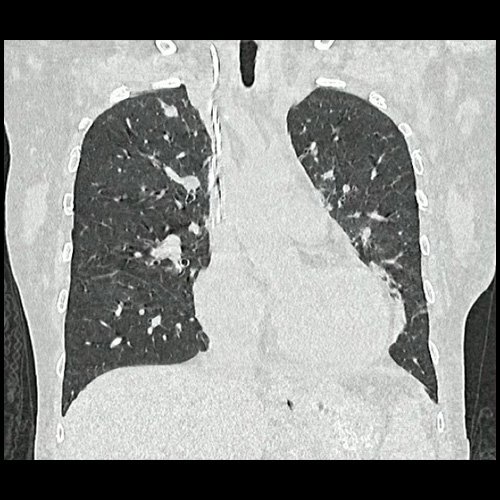

• TAC tórax (un mes atrás):La porción visualizada de la glándula tiroides es de características normales. Las estructuras vasculares paraaórticas son de características normales, permeables. La aorta ascendente, el cayado y la aorta descendente son de calibre y trayectoria conservados. Las estructuras venosas mediastinales: vena cava superior, vena cava inferior, venas pulmonares superiores e inferiores y venas ácigo-hemiácigos, son de calibre y trayecto conservado. La arteria pulmonar y sus ramas son de calibre y trayecto conservados.. Relación aórtico-pulmonar conservada. El corazón es de tamaño normal. El pericardio es de espesor conservado. El esófago es de calibre y trayecto normales. El mediastino está en posición central. Estructuras ganglionares pre y laterotraqueales, subcarinales, axilares bilaterales, aumentadas en número y de tamaño, algunas de ellas de rango megálico, destacándose una axilar izquierda con pérdida de la morfología habitual que mide 10 mm en su eje corto.

• TAC de tórax sin contraste - informe preeliminar (Dia 31):  Estudio artefactado por movimientos respiratorios de la paciente. Se observan múltiples lesiones nodulares sólidas, irregulares, heterogéneas, que se extienden por ambos campos pulmonares a predominio derecho, de manera periférica y subpleurales, asociadas a vidrio esmerilado, destacándose la de mayor tamaño en segmento lingular inferior que mide 12 mm x 16mm. Hallazgos que podrían corresponder en primera instancia a proceso inflamatorio infeccioso sin poder descartar secundarismo. Se sugiere control evolutivo.  Hallazgos no visualizados en Tc del día 05-08-2025, si se observan en TC del día 24-09-2025. Bulla subpleural paramediastinal, de 14mm, en segmento posterior del LSI. Leve derrame pleural, en esta ocasión, bilateral, de mayor jerarquía a derecha. Múltiples estructuras ganglionares pre y lateroaórticas, axilares bilaterales aumentada en número y de tamaño, de rango no megálico. Laminar derrame pericárdico.

TAC de tórax (internación previa)

TAC de tórax (Dia 31)